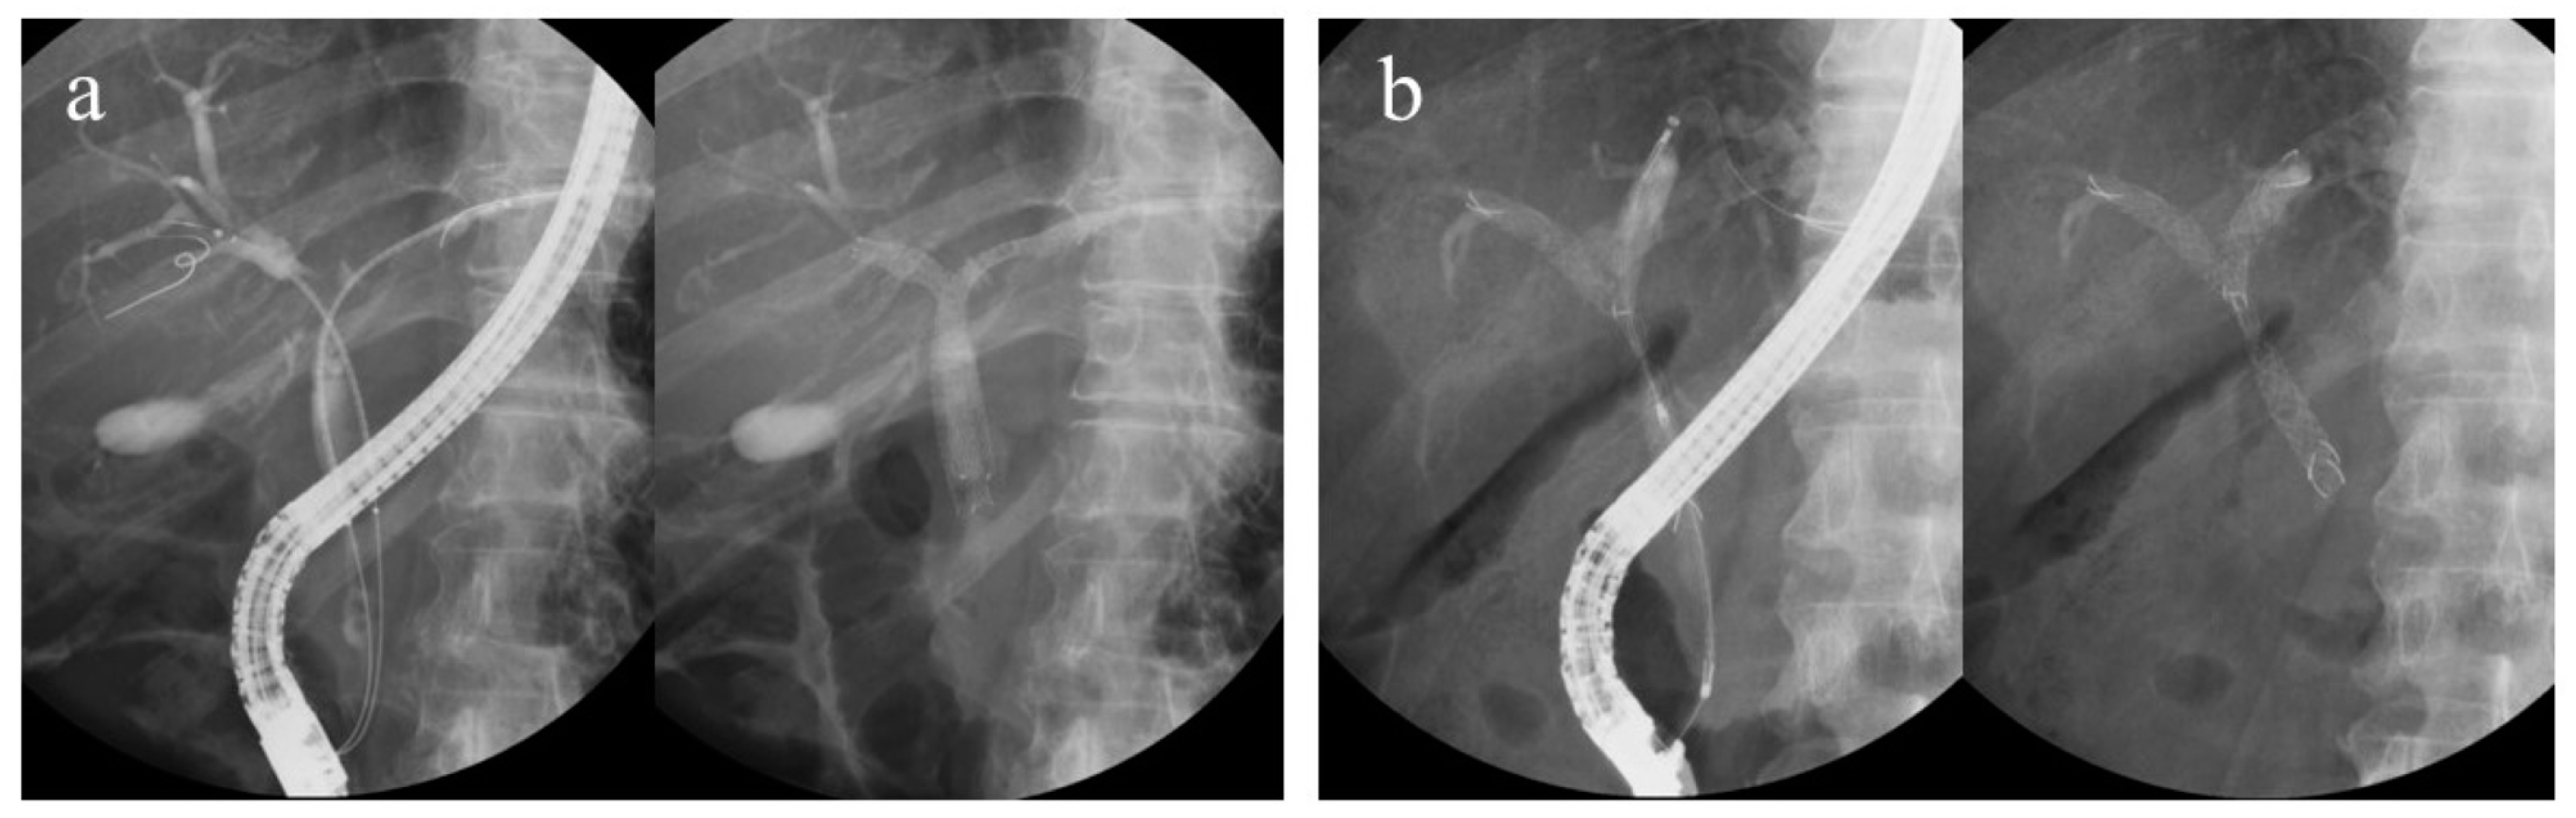

Regarding bilateral UMS placement using the ERCP, two stenting methods are used: side-by-side placement (SBS) and partial stent-in-stent placement (PSIS). SBS is a procedure in which two guidewires are placed in two branches of the intrahepatic bile duct (IHD), and then two stent deliveries are inserted and deployed sequentially. The routes of the two UMSs are independent of each other. Meanwhile, PSIS is a procedure in which the first stent is deployed, followed by another stent inserted through the mesh of the first stent and deployed (Figure 1). As a procedure, the PSIS is more complex.

Figure 1.

(a) Side-by-side placement and (b) partial stent-in-stent placement.